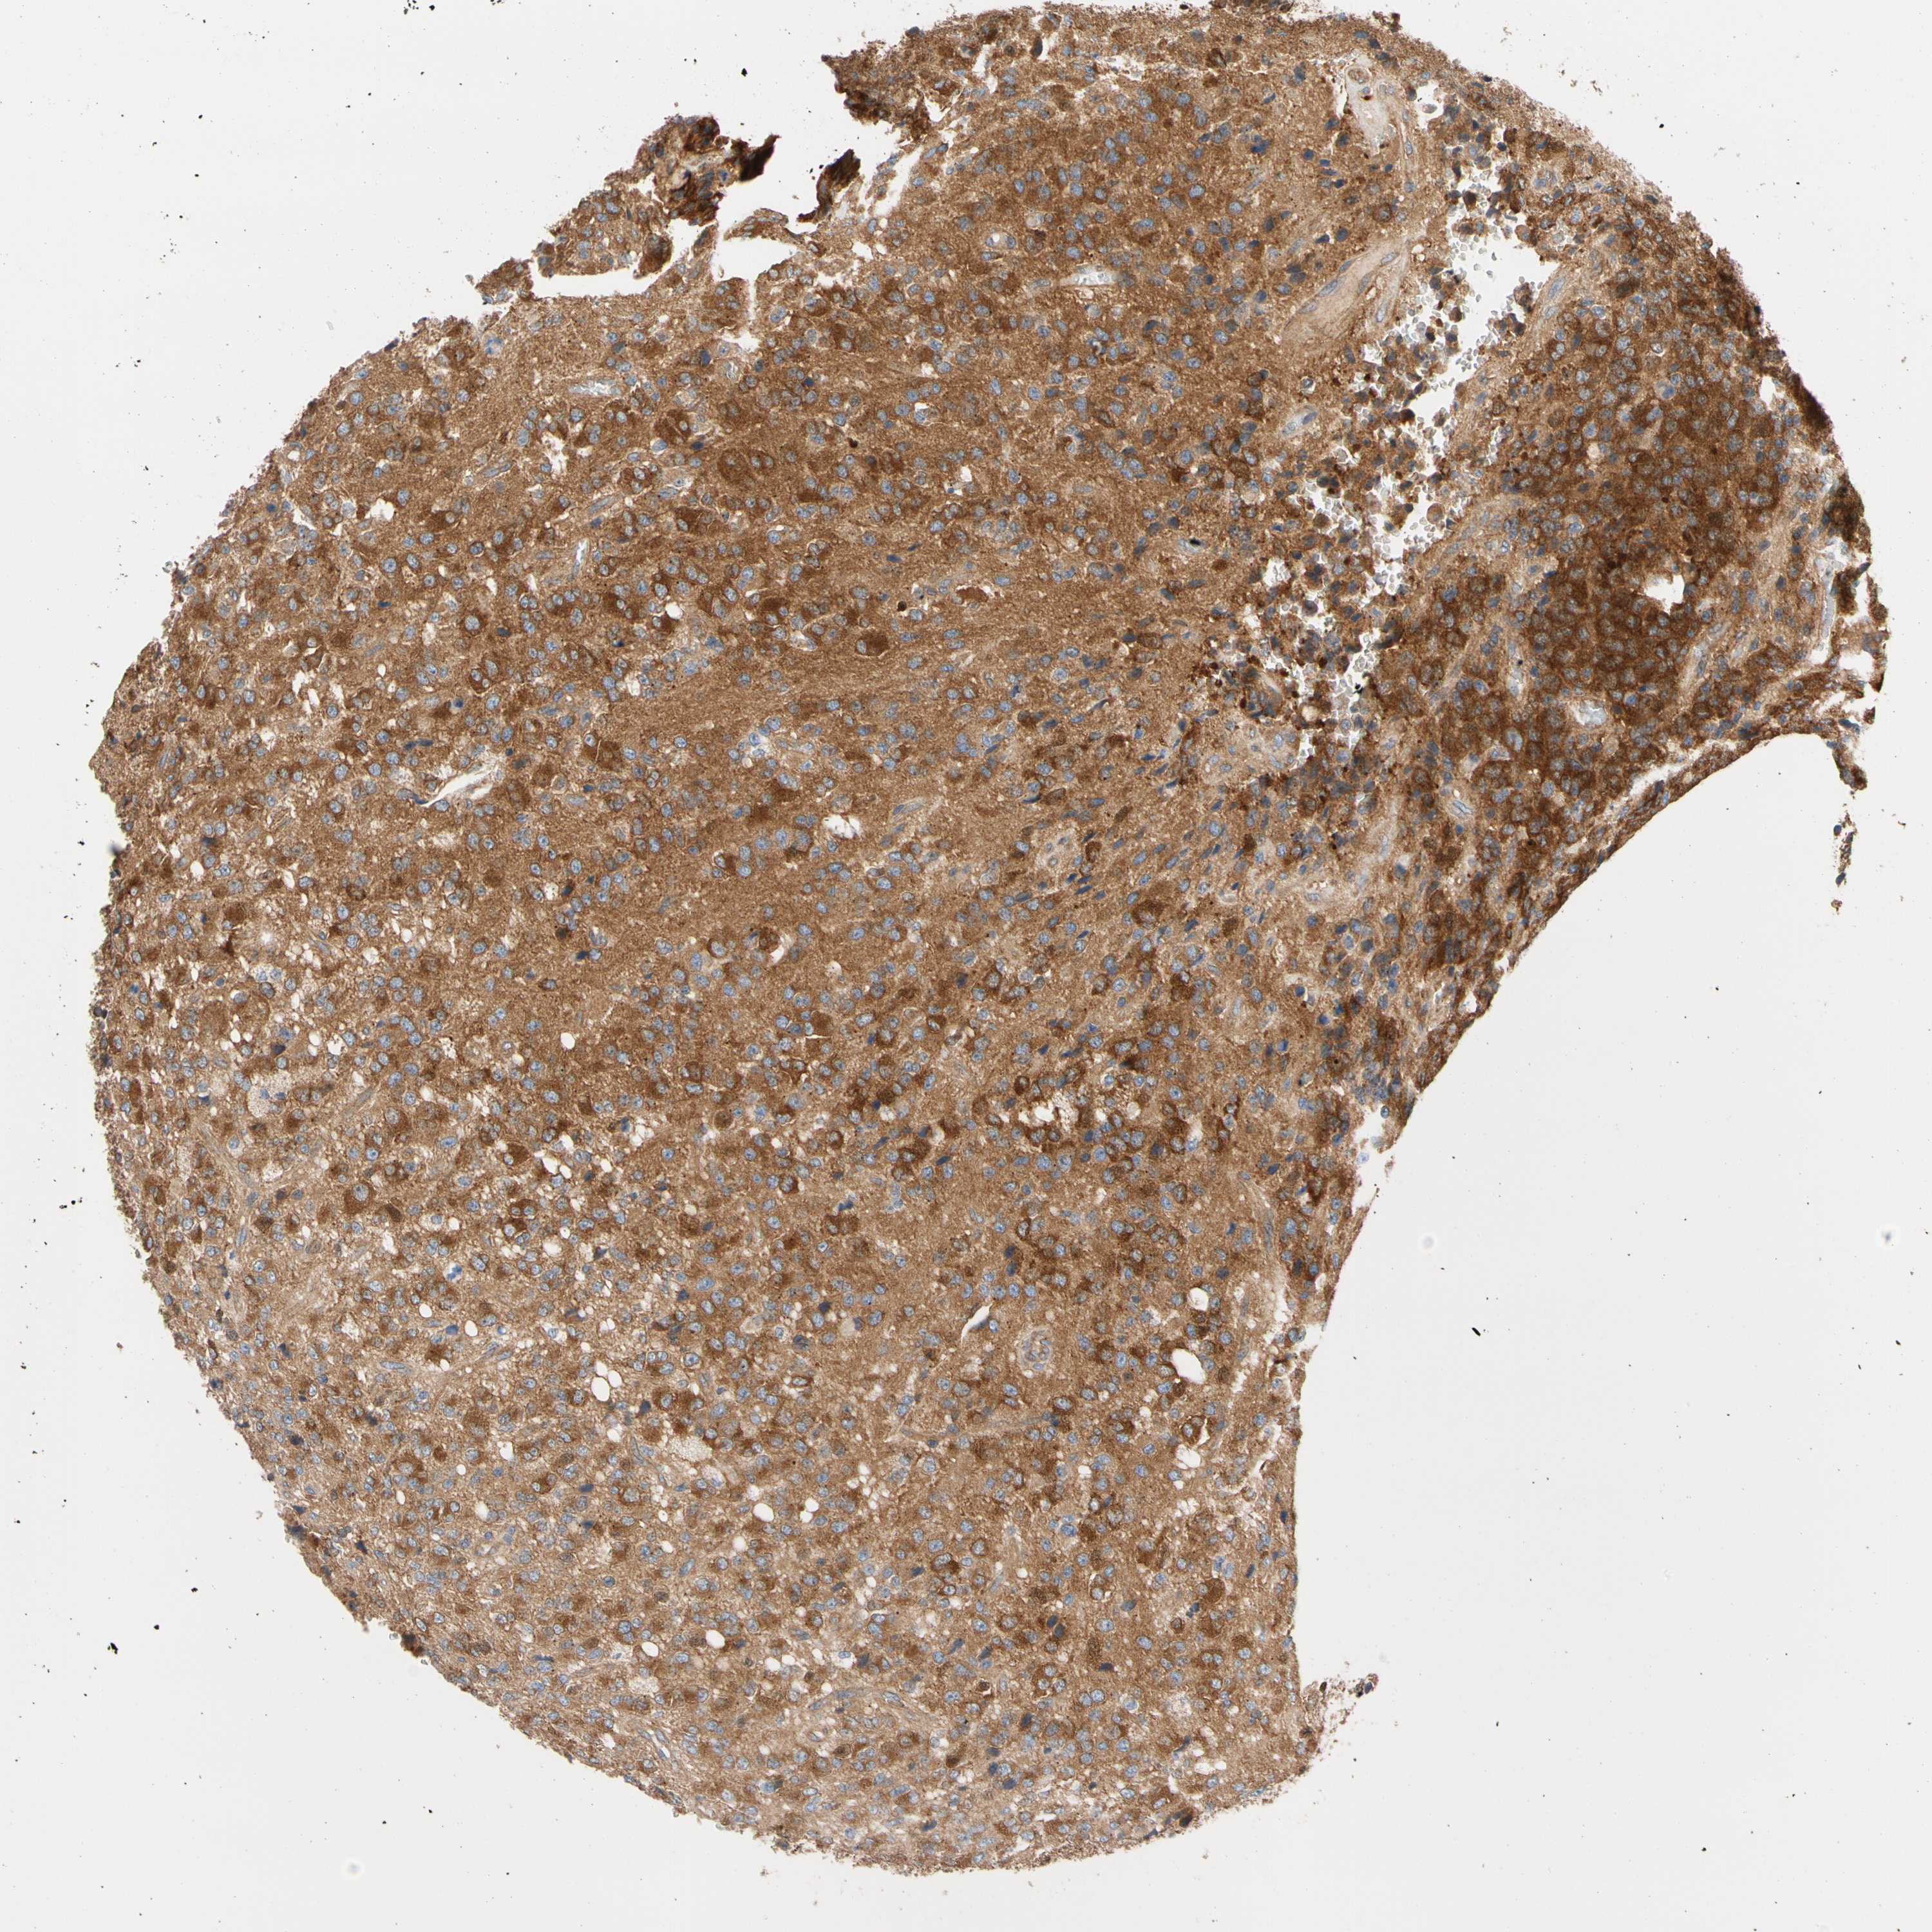

GLIOMA - Protein expressioni

A mouse-over function shows sample information and annotation data. Click on an image to view it in a full screen mode. Samples can be filtered based on level of antibody staining by selecting one or several of the following categories: high, medium, low and not detected. The assay and annotation is described here.

Note that samples used for immunohistochemistry by the Human Protein Atlas do not correspond to samples in the TCGA dataset.

Antibody stainingi

Antibody staining in the annotated cell types in the current human tissue is reported as not detected, low, medium, or high, based on conventional immunohistochemistry profiling in selected tissues. This score is based on the combination of the staining intensity and fraction of stained cells.

Each image is clickable and will lead to virtual microscopy that enables deeper exploration of all samples and also displays staining intensity scores, fraction scores and subcellular localization as well as patient and tissue information for each sample.

Antibody HPA003116

Antibody HPA024694

Antibody CAB004419

Staining

High

Medium

Low

Not detected

Intensity

Strong

Moderate

Weak

Negative

Quantity

>75%

75%-25%

<25%

None

Location

Nuclear

Cytoplasmic/membranous

Cytoplasmic/membranous,nuclear

Glioma, malignant, High grade

Glioma, malignant, Low grade